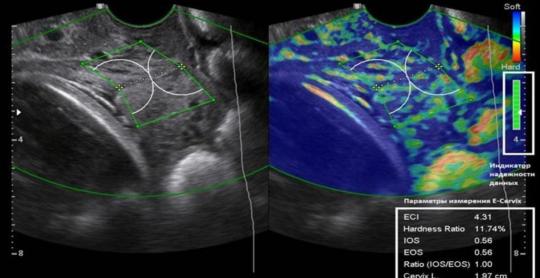

Journal of Clinical Medicine Research

Vol. 17, No. 11, Nov 2025, pages 618-633

By Saule Issenova et al.